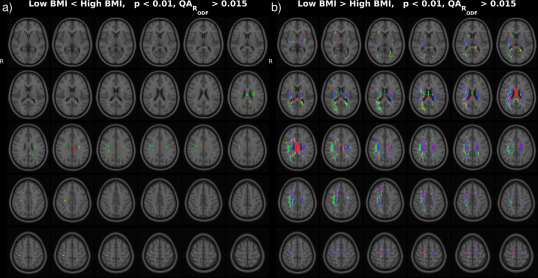

In the HCP dataset, ODFs correlate strongly with the demographic variable BMI. As expected, the ODFs negatively correlate (Fig. 7b) with BMI, indicating a loss of anisotropy with increasing BMI (Fig. 5a,b). This result is consistent with the well-established negative association between global white matter integrity and physical obesity (Mueller et al., 2011; Stanek et al., 2011; Verstynen et al., 2012; Gianaros et al., 2013; Verstynen et al., 2013). The fiber directions (Fig. 8a,b) identified from can be used to perform tractography (Fig. 8c,d). Resulting tracts (Fig. 8c,d) show a pronounced loss of anisotropy in the corticospinal tracts, the optic radiations and the right superior longitudinal fasciculus. These results are corroborated by the existing methods TBSS (Fig. 9a,b, S2a,b), Connectivity-based fixel enhancement (Fig. 9c,d, S2c,d) and local connectometry (Fig. 9e,f, S3a,b). The volume of positive findings of correlation with BMI is largest when using the full ODF information with the ODF approach (Fig. 9). In addition, in a test of specificity, no voxels are found to correlate with randomly permuted BMI (Fig. S4).

The individual variability of ODFs can be caused by ODF reconstruction errors due to image artifacts (Fig. S5.1), registration errors and individual differences in brain structure (Fig. S5.3-4). In the HCP ODFs individual variability due to the first two of these contributions is limited by the low number of artifacts and the high image resolution in the HCP DWI images. As a result, ODF correlations of BMI identified with ODF ((Fig. 9g,h, S3c,d)) and ODF (Fig. 9i,j, 7) are similar in this dataset. However, in a dataset with higher individual variation, notable improvement of ODF over ODF PCA can be observed (Baete et al., 2016a).

Several methods exist to analyze populations of diffusion MRI datasets, typically working on a reduced dimensionality subset of the diffusion data. TBSS (Jbabdi et al., 2010), limiting the analysis to a projection to a tract skeleton, succeeds in identifying the tracts most significantly correlated with BMI (analysis of FA, Fig. 9a,b, S2a,b) but misses the full extent of the correlations. The Connectivity-based fixel enhancement (Raffelt et al., 2015) and Connectometry (Yeh et al., 2016) approaches do include more of the available information and hence perform better than the TBSS method (Fig. 9c,d, S2c,d (Fixel enhancement) and 9e,f, S3a,b (Connectometry) vs 9a,b, S2a,b (TBSS)).

None of the above methods however capitalizes on the full ODF information. This in contrast to the approach presented in this paper. The ODF approach indeed identifies a larger volume of significant findings (227 cm3) than the existing methods tested here (TBSS 17 cm3, Connectivity-based fixel enhancement 15 cm3 and Connectometry 212 cm3, Fig. 9b,d,f,h,j). That is, by analyzing the full ODF information and not reducing the dimensionality of the diffusion data, as is commonly done, the ODF approach is able to pick up on smaller significant changes, better grasping the full extent of the significant findings. Limitations on computational power and diffusion acquisitions (e.g. DTI) which inspired the data reduction of older methods no longer exist. It is hence advisable to maximize the amount of information included in the analysis as in the approach presented here.